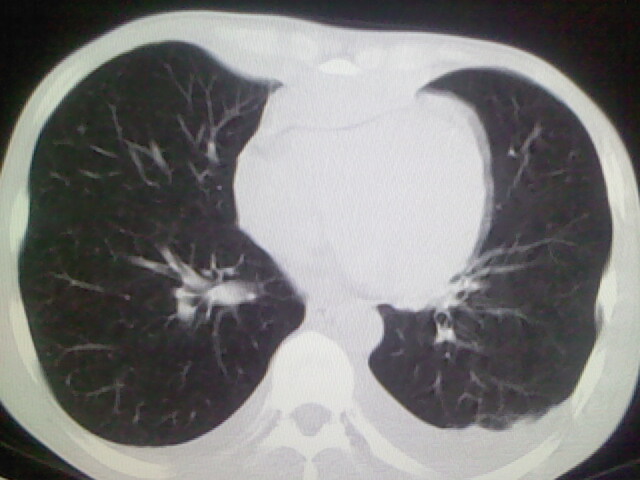

以下是引用杀毒软件在2008-9-3 6:11:00的发言:[br]侵袭性胸腺瘤------一般不侵到气管旁[br][br]考虑----纵隔淋巴瘤,心包及胸膜受累

以下是引用随光逐影在2008-9-3 7:07:00的发言:[br]1)考虑淋巴瘤可能。2)双侧胸腔积液(以左侧为甚)。3)心包积液。